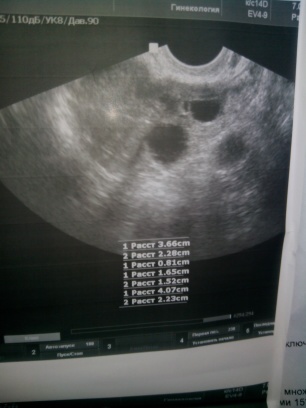

На 18 д.ц. все таки ради интереса из-за ощущений сходила еще раз на УЗИ:

В ЛЯ ЖТ 15*16мм, жидкость в пзмп.